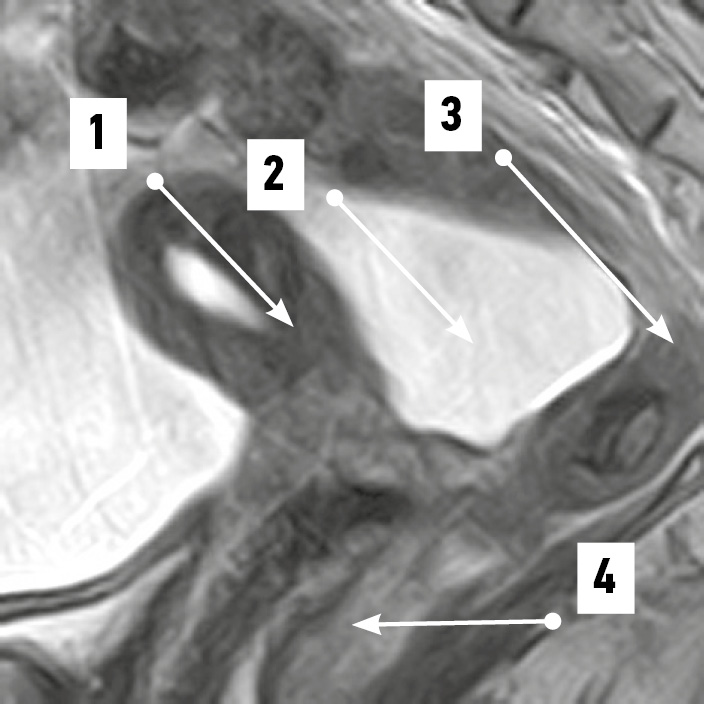

По результатам МРТ-анализа при положениях матки anteversio-anteflexio надвлагалищный участок прямой кишки в половине случаев (52,4%) был извит во фронтальной плоскости (рис. 1). В 38,1% случаев кишка имела ход, соответствующий вогнутости крестца (рис. 2), ещё в 9,5% сагиттальный изгиб кишки был значительно выражен. Расстояние между маткой и прямой кишкой в надвлагалищном участке в среднем составило 5,93±0,97 мм. Здесь прослеживался значительный разброс минимальных и максимальных величин, свидетельствовавший о разнообразии положения органов: от их крайней степени близости — 0,00 мм (рис. 3) до удалённого положения — 17,00 мм (рис. 4). Последнее может служить анатомической предпосылкой для положения петель тонкой кишки в относительно широком прямокишечно-маточном углублении.

Рис. 1. Извитой во фронтальной плоскости надвлагалищный участок прямой кишки. Магнитно-резонансная томограмма органов таза в режиме SG T2: 1 — матка; 2 — надвлагалищный участок прямой кишки (извит во фронтальной плоскости); 3 — влагалищный участок прямой кишки; 4 — крестец; 5 — прямокишечно-маточное пространство. / Fig. 1. Supravaginal segment of the rectum convoluted in the frontal plane. SG T2-magnetic resonance imaging of pelvic organs: 1 — uterus; 2 — supravaginal segment of the rectum (convoluted in the frontal plane); 3 — vaginal segment of the rectum; 4 — sacrum; 5 — rectal–uterine space.